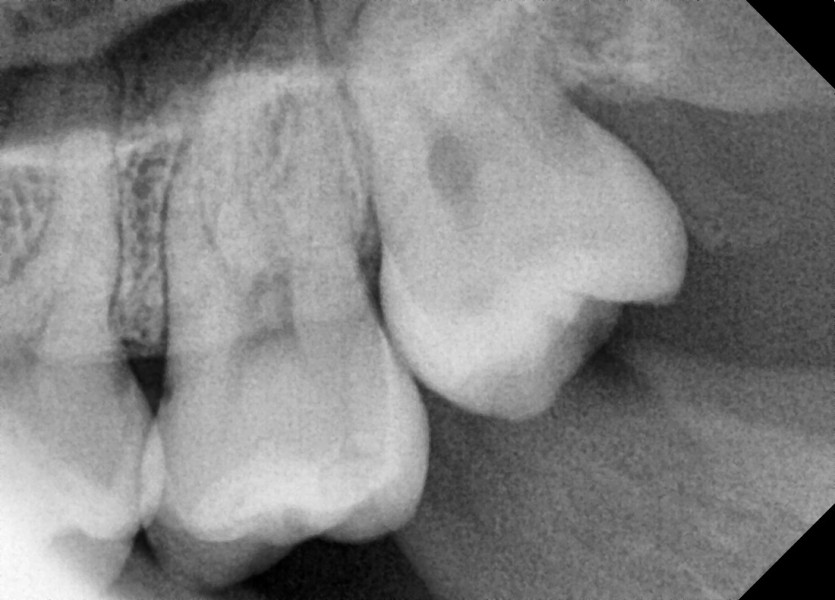

#28,38,48 사랑니 발치

구강 외과 전문의가 당일 발치했습니다.